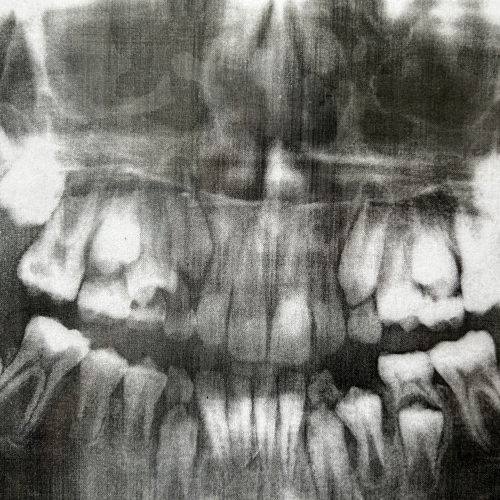

Wie putzt man richtig?Wie putzt man richtig?Daniela zeigt es vor.Daniela zeigt es vor.Die 4 Säulen der ZahngesundheitDie 4 Säulen der ZahngesundheitSelbst gebastelt und zum MitnehmenSelbst gebastelt und zum MitnehmenSo putzt man richtigSo putzt man richtigZusammenfassungZusammenfassungZahnröntgen eines KindesZahnröntgen eines KindesGebiss zum ÜbenGebiss zum ÜbenGruppenfoto mit BürstlGruppenfoto mit Bürstl